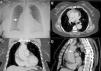

Frontal chest X-ray (A) shows enlargement of the right heart border. Transaxial, contrast-enhanced computed tomography (B) image showing dilatation of the ascending aorta end evidence of type A aortic dissection (*). Coronal (C) and sagittal oblique (D) contrast enhanced computed tomography images showing a type A aortic dissection (*) and the point of intimal tear (arrow).

A contrast-enhanced chest computed tomography (CT) was performed (Fig. 1B–D) and identified a Stanford type A aortic dissection extending to the level proximal to the brachiocephalic trunk. The aorta was dilated (maximum transverse diameter of 6.6cm) and two regions of intimal rupture, both in the distal ascending aorta, were identified. The patient was kept on continuous monitoring in the Intensive Care Unity, aiming to achieve a strict control of blood pressure and heart rate. Syphilis serology was requested, despite the low probability of syphilitic aortitis, revealing negative VDRL and positive fluorescent treponemal antibody-absorption (FTA-ABS) test. The patient denied a previous diagnosis of syphilis or prior treatment for this condition.